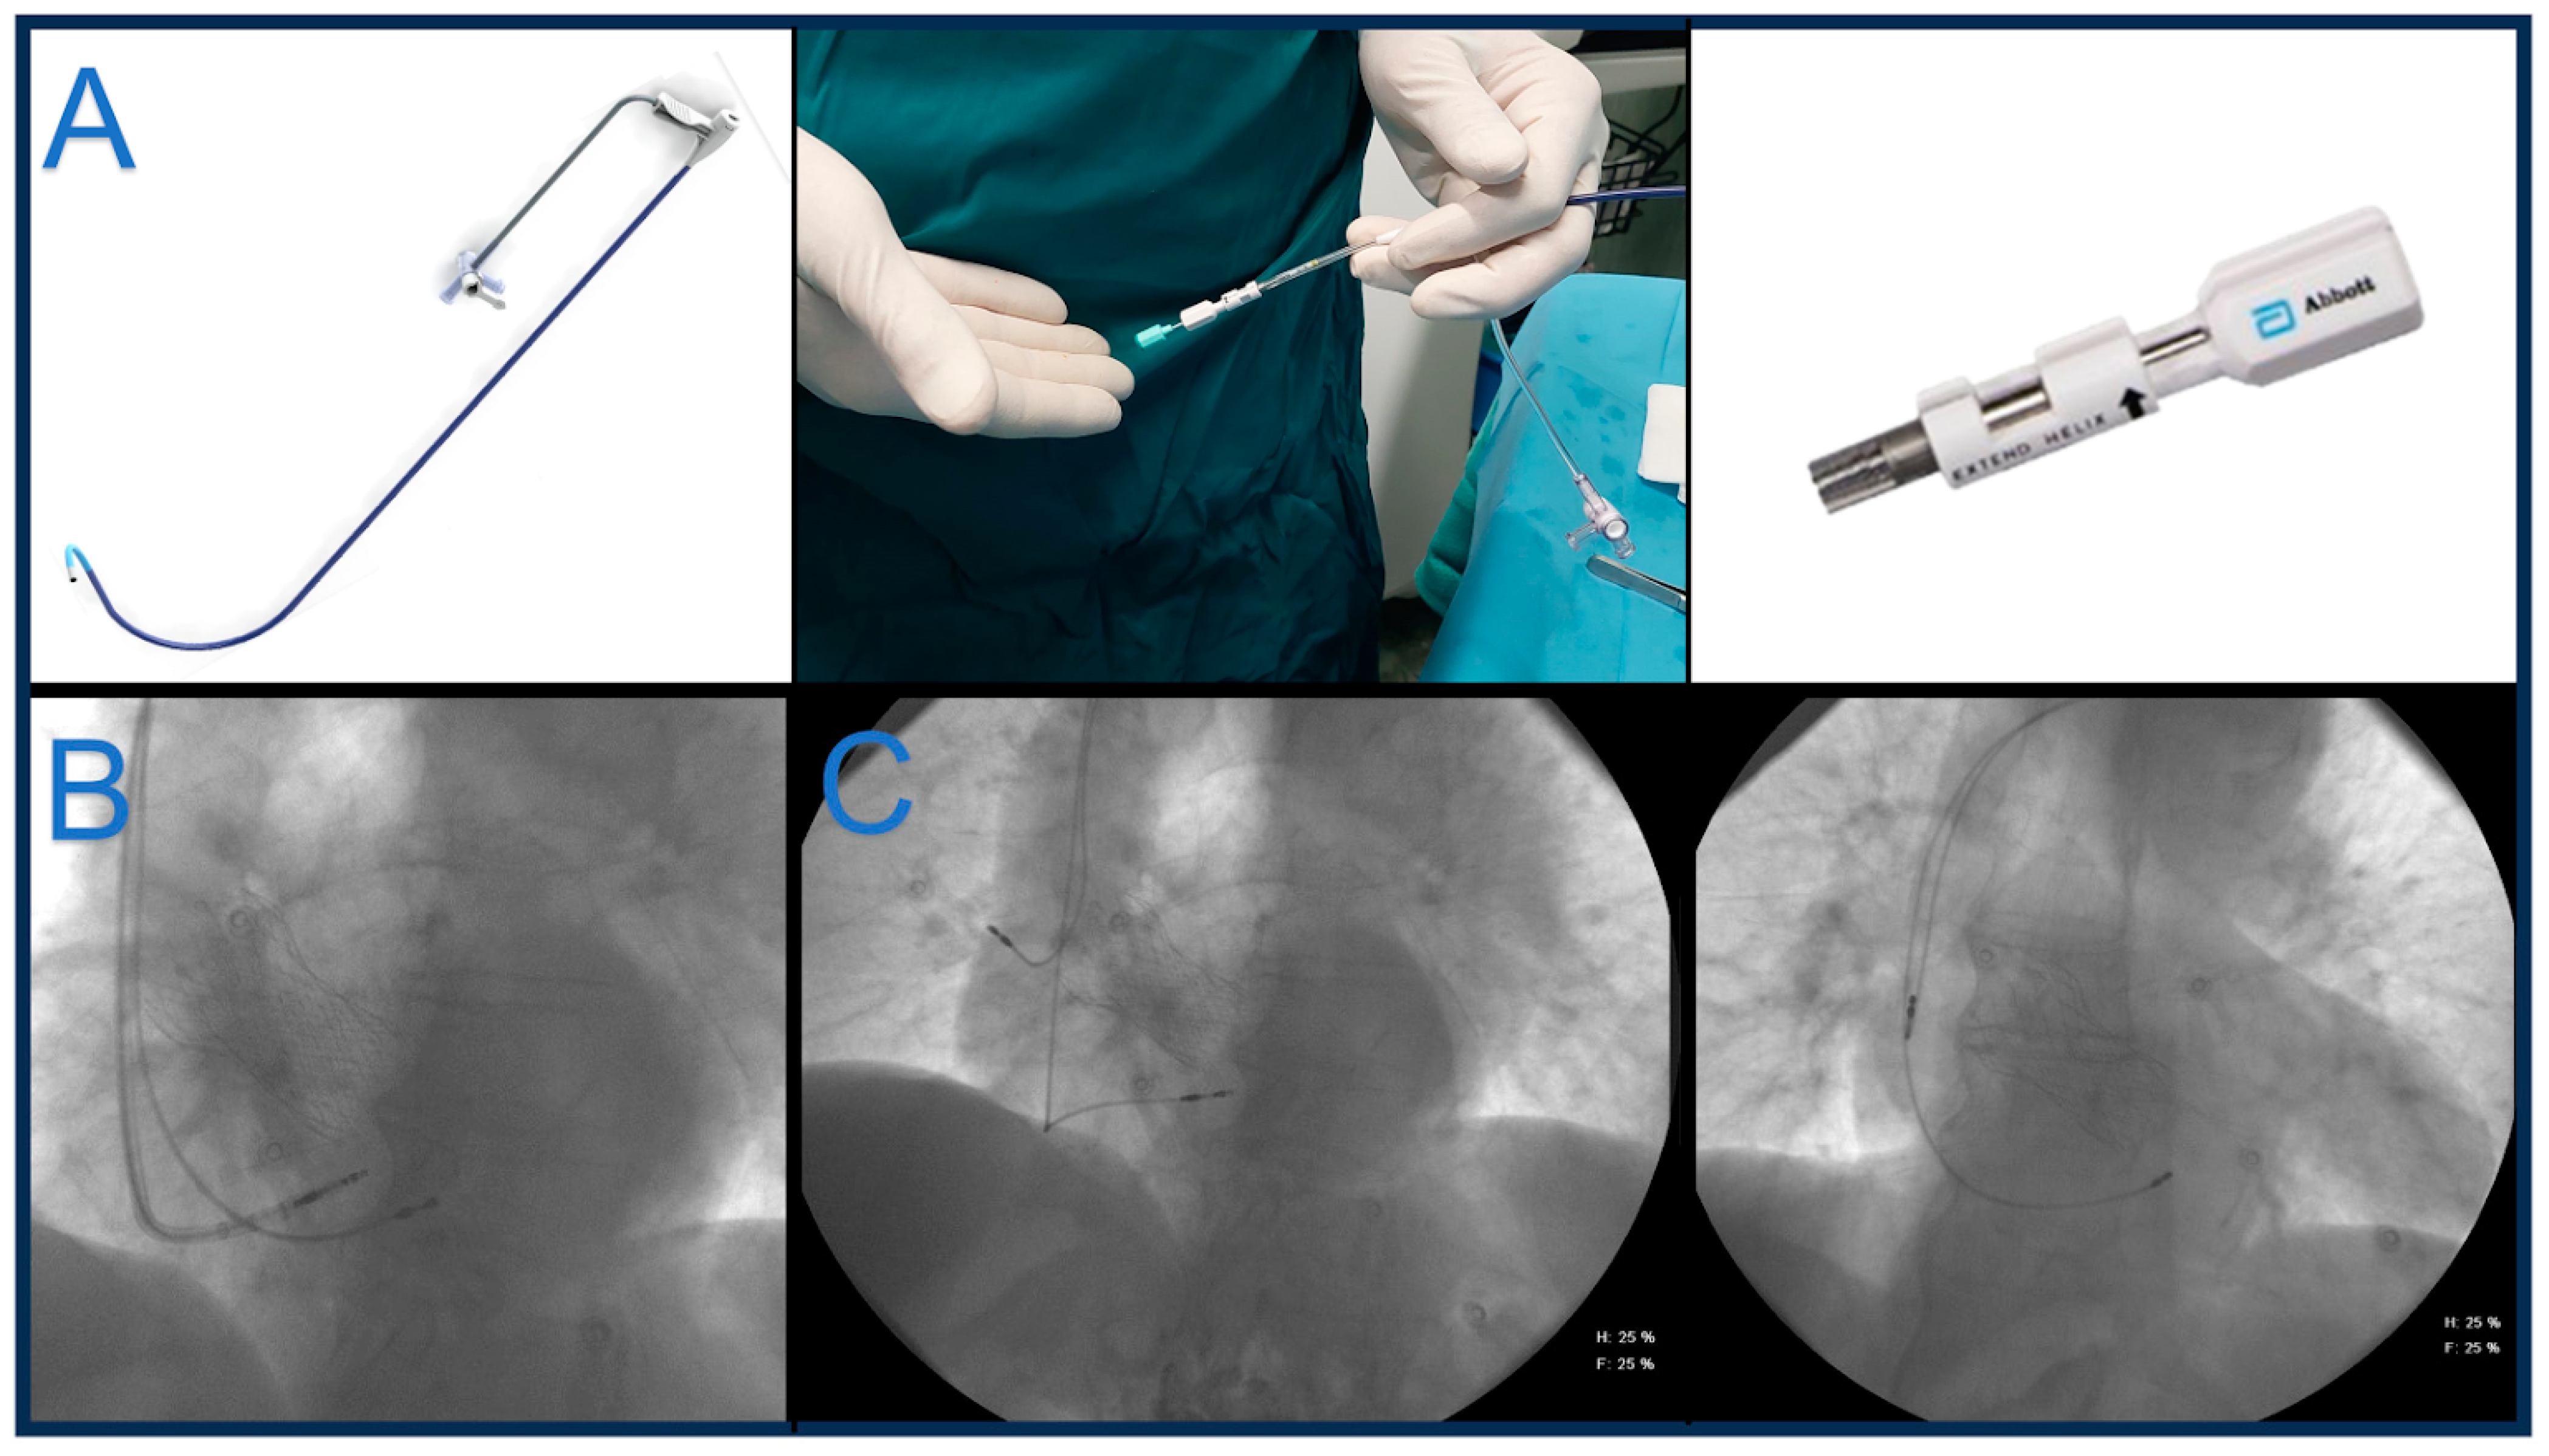

3. Lumenless Lead

3.1. Medtronic

4.4. Tendril™ STS 2088TC (Abbott)

- Le Polain de Waroux, J.B.; Wielandts, J.Y.; Gillis, K.; Hilfiker, G.; Sorgente, A.; Capulzini, L.; Geerts, B.; Knecht, S.; Duytschaever, M.; Tavernier, R. Repositioning and extraction of stylet-driven pacing leads with extendable helix used for left bundle branch area pacing. J. Cardiovasc. Electrophysiol. 2021, 32, 1464–1466. [Google Scholar] [CrossRef] [PubMed]